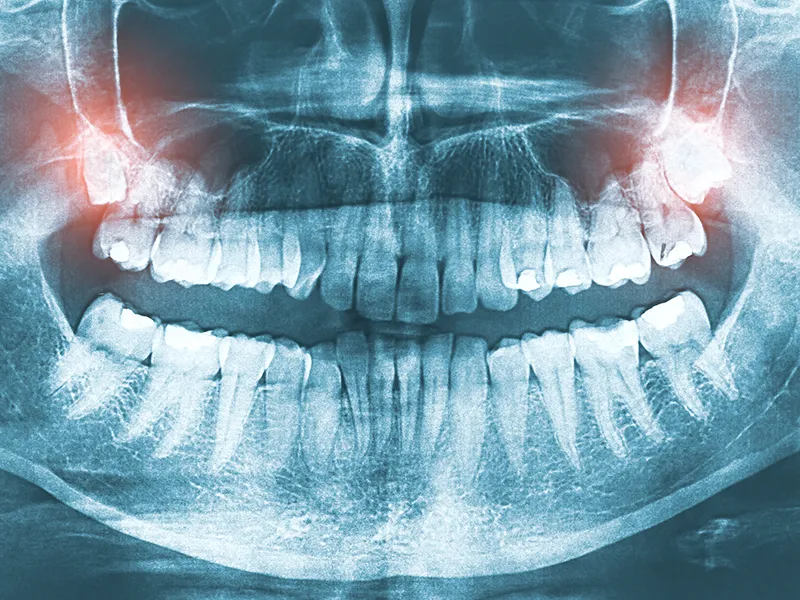

Sometimes, dentists recommend extracting wisdom teeth before problems arise. Preventive removal is common when X-rays reveal that the teeth are likely to cause future issues, such as impaction, misalignment, or damage to other teeth. Early extraction can often prevent pain, infection, and more complicated dental procedures down the road.

1. Consultation and diagnosis: Your dentist or oral surgeon will thoroughly examine your mouth and take X-rays to evaluate the position, size, and condition of your wisdom teeth. This helps determine the best approach for extraction and whether any complications are likely.